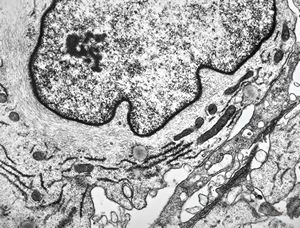

M, 11y. | mycosis fungoides v.s. - cerebriform nucleus of Sézary cell